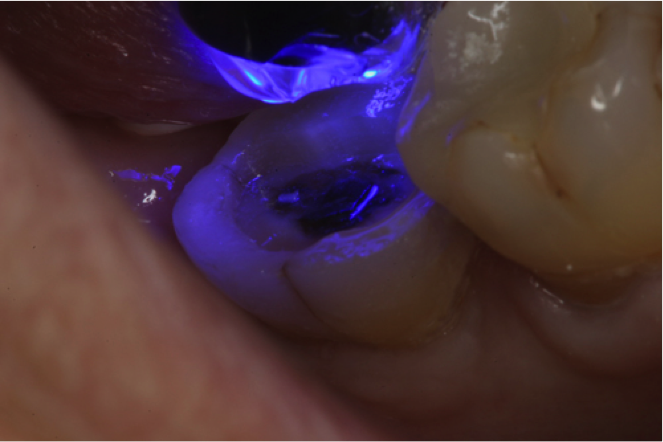

Fig. 4  Light-curing to remove the oxygen-inhibited layer.

Figure 4

If a temporary restoration is being used, and two appointments are necessary, then the oxygen-inhibited layer should be removed by using an alcohol wipe or applying surgical lubricant over the tooth. Light-curing will then eliminate the oxygen-inhibited layer (Figure 4). This will also prevent any resin-based temporary material from sticking to the tooth. This is not necessary, however, if a same-day restoration created with a chairside milling machine is being delivered.